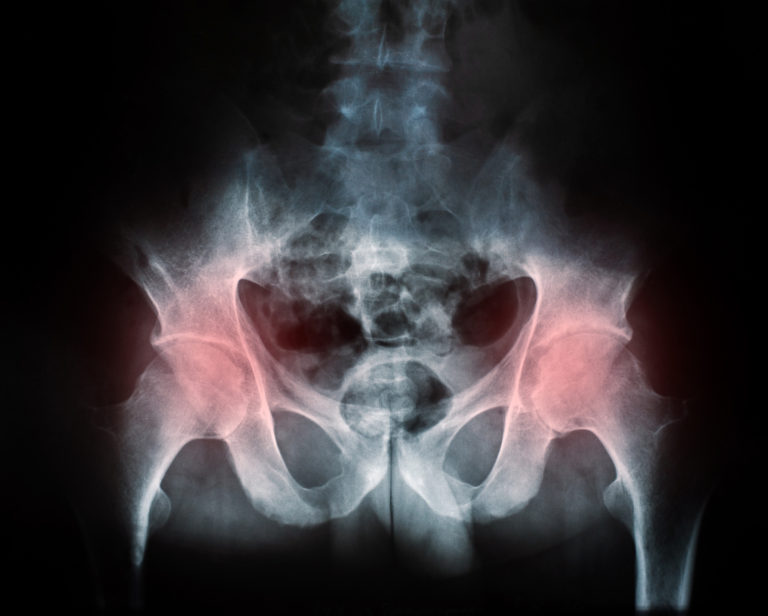

Dislocation After Hip Replacement OrthoInfo AAOS Is There A Recall On Zimmer Hip Replacements Fda is alerting health care professionals and patients about the risk of thigh bone fractures after surgery with zimmer. On july 2, 2024, zimmer biomet initiated a voluntary recall to update instructions for use for the cpt hip system due to an. Review this notification and ensure that affected personnel are aware of. Letter states reason for recall, health risk. Is There A Recall On Zimmer Hip Replacements.

Hip Replacement Complications Total and Partial Surgeries Is There A Recall On Zimmer Hip Replacements The fda is getting the word out regarding a recall effort from zimmer biomet related to its discontinued cpt hip implant and. Fda is alerting health care professionals and patients about the risk of thigh bone fractures after surgery with zimmer. On july 2, 2024, zimmer biomet initiated a voluntary recall to update instructions for use for the cpt hip. Is There A Recall On Zimmer Hip Replacements.